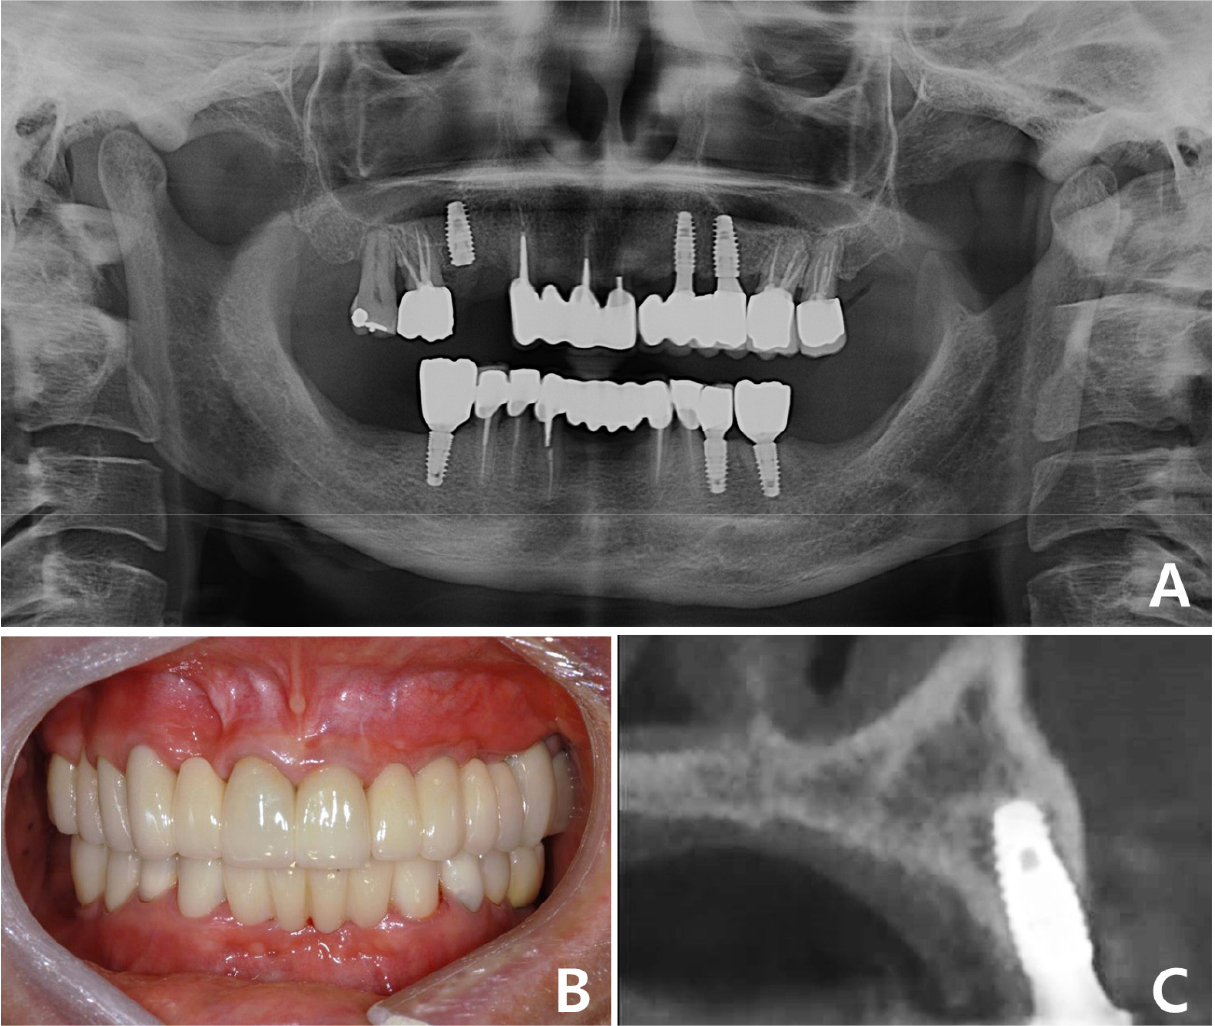

After a sufficient remodeling period of six months, the surgical site was evaluated as stable, and healing abutments were connected. The final 4-unit implant-supported FPD with a mesial cantilever was installed after the provisional phase (Fig. 8A, 8B). All procedures regarding implantation of allogeneic block-bone grafts were successfully performed, and no surgical-site complications were observed on CT three years postoperatively (Fig. 8C). The patient was satisfied with the aesthetic and functional outcomes of full-mouth rehabilitation using implant-supported FPDs.

Case 2: Intraoral and radiographic views of grafted site. (A) Sufficient bone bed for implantation is observed after block-bone grafting, (B) Two implants have been placed and submerged at the grafted site, (C) Sagittal CBCT image of the grafted site before implantation, (D) Sagittal CBCT image of the grafted site after implantation. CBCT, cone-beam computed tomography.